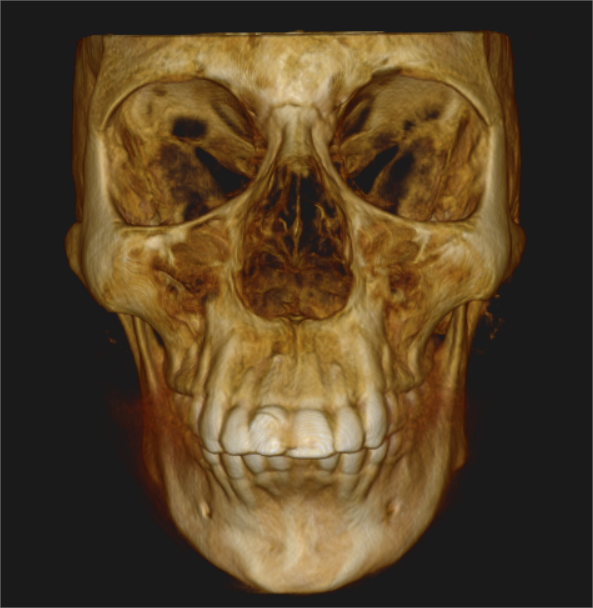

It encompasses various imaging techniques, including traditional x rays such as OPG, CEPH and advanced imaging like Cone beam computed tomography (CBCT).

These methods visualise teeth and bone providing crucial diagnostic information.

Cone Beam Computed Tomography (CBCT)